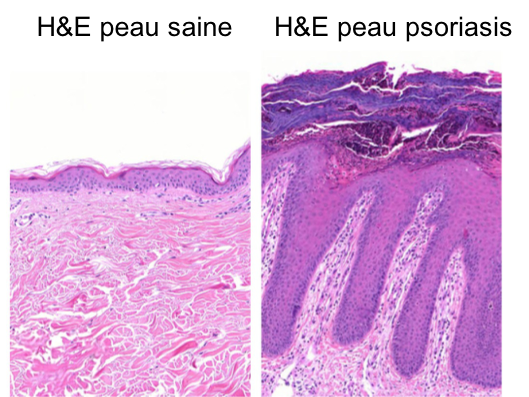

Notre laboratoire vise à définir les mécanismes moléculaires et biochimiques à la base des maladies inflammatoires de la peau, en prenant le psoriasis comme pathologie de référence.

Le psoriasis est une maladie très fréquente (environ 2-3 % de la population), qui débute généralement tôt dans la vie et évolue en maladie chronique. L'aspect inesthétique des lésions provoque fréquemment des problèmes psychologiques. Le psoriasis est également reconnu comme facteur de risque pour plusieurs comorbidités (troubles associés à la maladie), notamment la dépression, le diabète et les maladies cardiovasculaires.

Les interactions entre les cellules du système immunitaires et les cellules résidentes de la peau (les kératinocytes et les cellules endothéliales) jouent un rôle clé, mais encore peu connu, dans le développement du psoriasis et de ses comorbidités.